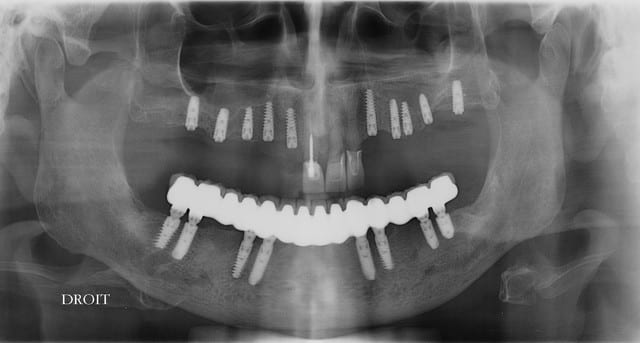

ouarf, mdr, l'implant en 47 est lingualé et tous les autres à partir du secteur antérieur partent sur la droite...comme pour tous les droitiers....

Professeur Pluton, tu devrais être plus cool avec les confrère moins doué que toi, en fait je me suis laissé guidé guidé par l'os et l'axe de la future prothèse mais bien sur, à main levée, puisque je n'ai pas les compétence pou me servir d'un outil geek.

Il me semble tout à fait normal que 47 n'ai pas la même inclinaison que 46 dans le sens vestibulo lingual...

A ce sujet, plutôt que de looker l'axe de 47, jette un œil sur 26 .... il ne s'agit pas de montrer que je suis le meilleur, mais que des techniques simples et bien raisonnées permettent d'obtenir des résultats corrects et reproductible, et ce par n'importe quel dentiste consciencieux.

pour 26 (comme pour les 17 autres implants de ce cas) flapless intégral (même pas de puch), foret initial directement à travers la gencive) et uniquement des éponges de Gelatemp là où c'était nécessaire.

je mets les coupes et les radios post op...